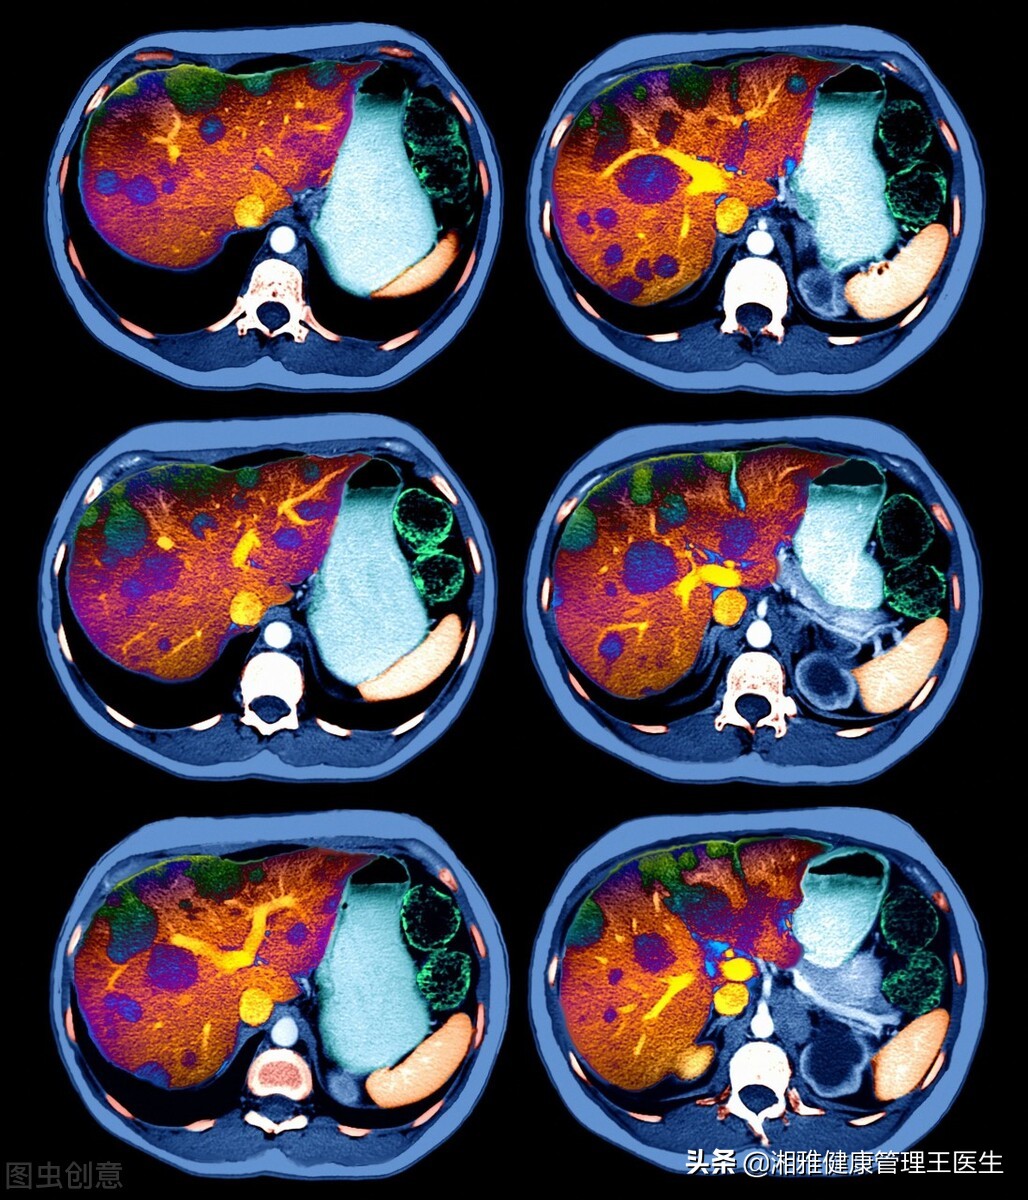

#肝癌来临是否有“预示”#

肝癌来临时有什么症状?

肝癌筛查,早期发现,早期治疗是最好的措施。

如何筛查?

肝癌筛查的方法包括:肝脏彩超,肝纤维化检测,肝癌的肿瘤标志物检测等。